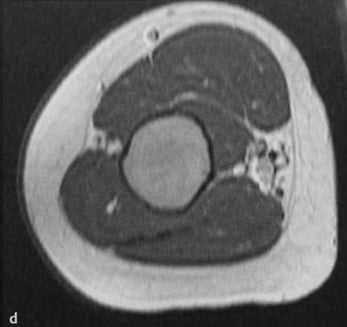

a-d Фиброзная дисплазия. Женщина 48 лет с фиброзной дисплазией, поражающей дистальный отдел плечевой кости: a) На рентгенограмме диафиза плечевой кости определяется кистозное географическое поражение с пузырным расширением. Типичное изображение в виде «битого стекла»;

b) Аксиальная Т1- взвешенная последовательность. Гипоинтенсивное поражение с истончением кортикального слоя.

c) Т2-взвешенная последовательность. Гипоинтенсивный сигнал по отношению к нормальной жировой ткани костного мозга;

d) Т1-взвешенная последовательность после введения гадолиния. Гомогенное на¬копление контрастного вещества в области поражения.